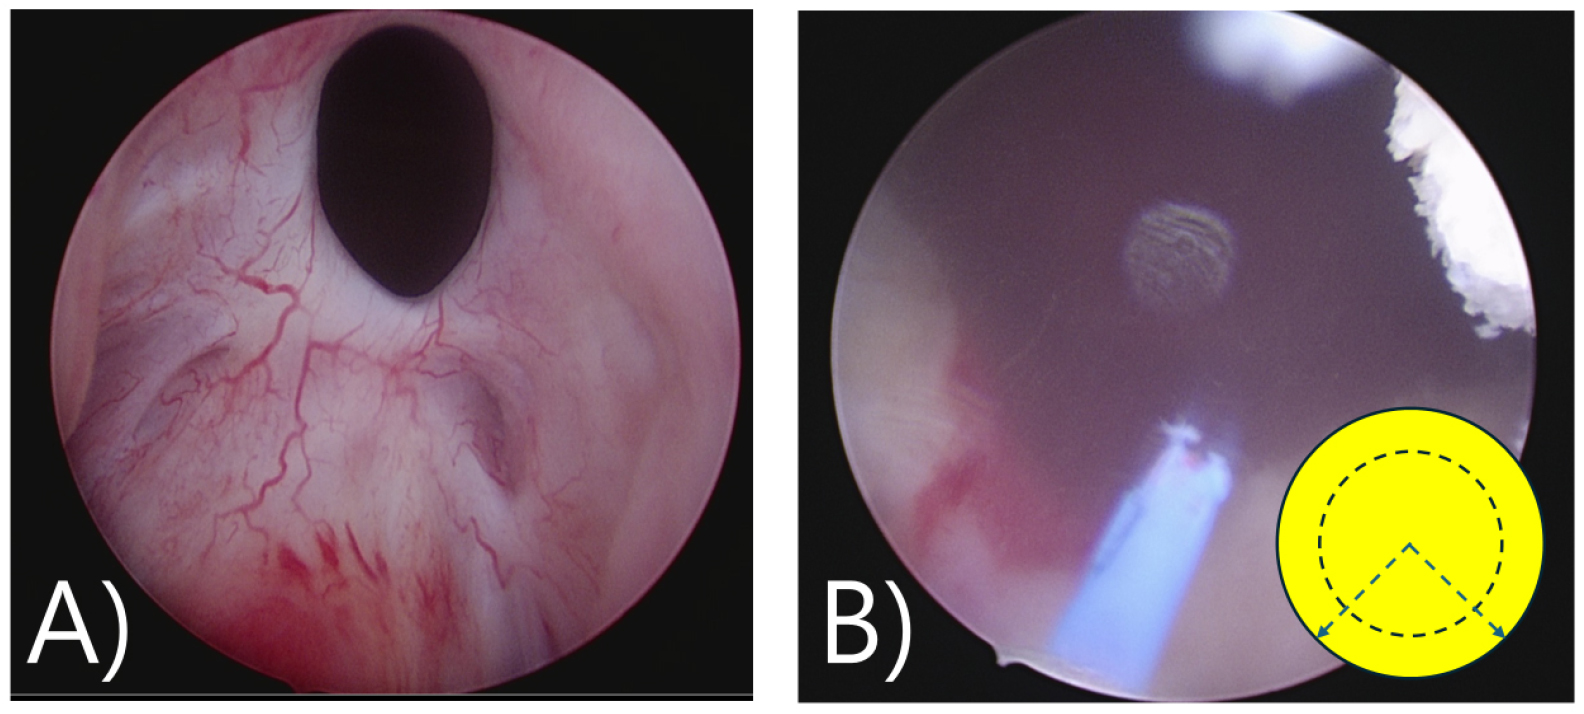

수술과정

수술은 척수 마취하에 하에 협착된 부위를 Collins knife를 이용하여 방광목 절개를 시행하였으며 fibrotic tissue에 여러 방향으로 깊은 절개를 하였다. 이후 주변에 남은 전립선조직을 resectoscope (loop type)으로 절제(reTURP)하였다 [그림 10(A)-(D)]. 수술 후 1년 반 이상 특이 소견 없이 경과관찰 중이다.

1차 요도절개; 수술은 전신마취하에 협착된 부위를 홀뮴레이져를 이용하여 방광목 절개를 시행하였다. 5시 7시 방향으로 깊은 절개를 하여 방광목을 충분히 넓혀 주었다.

2차요도절개; 추적관찰 중 방광목 폐색이 다시 진행(1차 요도절개후 1년 6개월 경과) 되었고 이전보다는 심하지 않았으나 배뇨증상의 완화를 위해서 2차 요도절개를 시행하였다. 이전 절개 부위인 5시 7시의 방광목의 membrane이 다시 붙는 양상으로 진행되어 다시 홀뮴레이져를 이용하여 넓은 환상절개를 시행하였다. 환자는 2차 수술 후 특이소견없이 경과관찰 중이다.